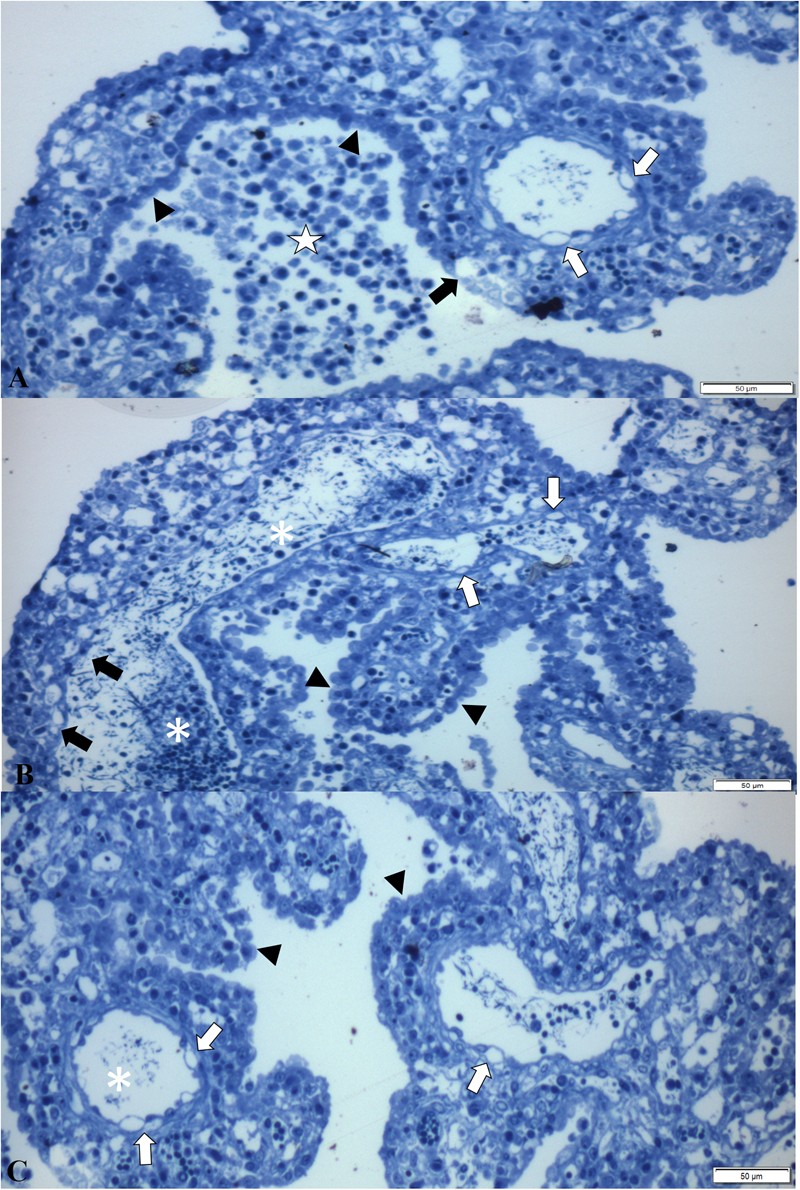

Figure 6

Semithin evaluation of the choroid plexus of piglets naturally infected with SVA. There is non-suppurative choroid plexitis (★), ballooning degeneration of endothelial cells (open arrows) of fenestrated capillary, degeneration (closed arrow) and swelling of (arrow heads) ependymocytes (A). Observe severe accumulations of macrophages and lymphocytes admixed with fibrin in the lumen (*) of a fenestrated capillary, necrosis (closed arrow) and degeneration (open arrows) of endothelial cells, with swelling and thickening (arrow heads) of ependymocytes (B,C). New methylene blue stain Bar, A-C, 50 µm.